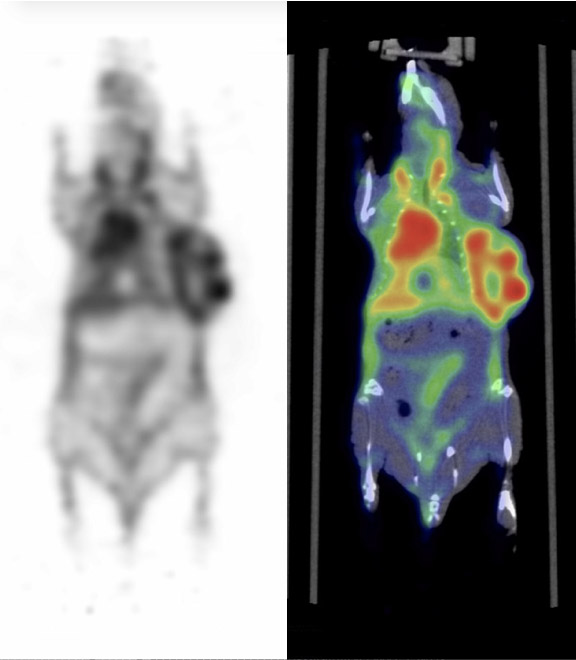

CASE 7: PET/CT cardiac imaging after myocardial ischemic injury

• Courtesy of: Shanxi Medical University, Taiyuan, Shanxi

Research objective: Evaluate cardiac function after myocardial ischemic injury by enhancing angiogenesis and myocardial metabolism. Investigate whether human endometrium-derived stem cells (hEMSCs) can be used for cardiac repair after ischemic injury and their possible underlying mechanisms.

Animal model: Female nude rats (180-250g)

Acquisition protocol: Imaging start 40 min after FDG injection (~ 7 MBq). CT imaging: 20s. PET imaging: 10 min static

Image analysis: PMOD 4.0 module PCARD